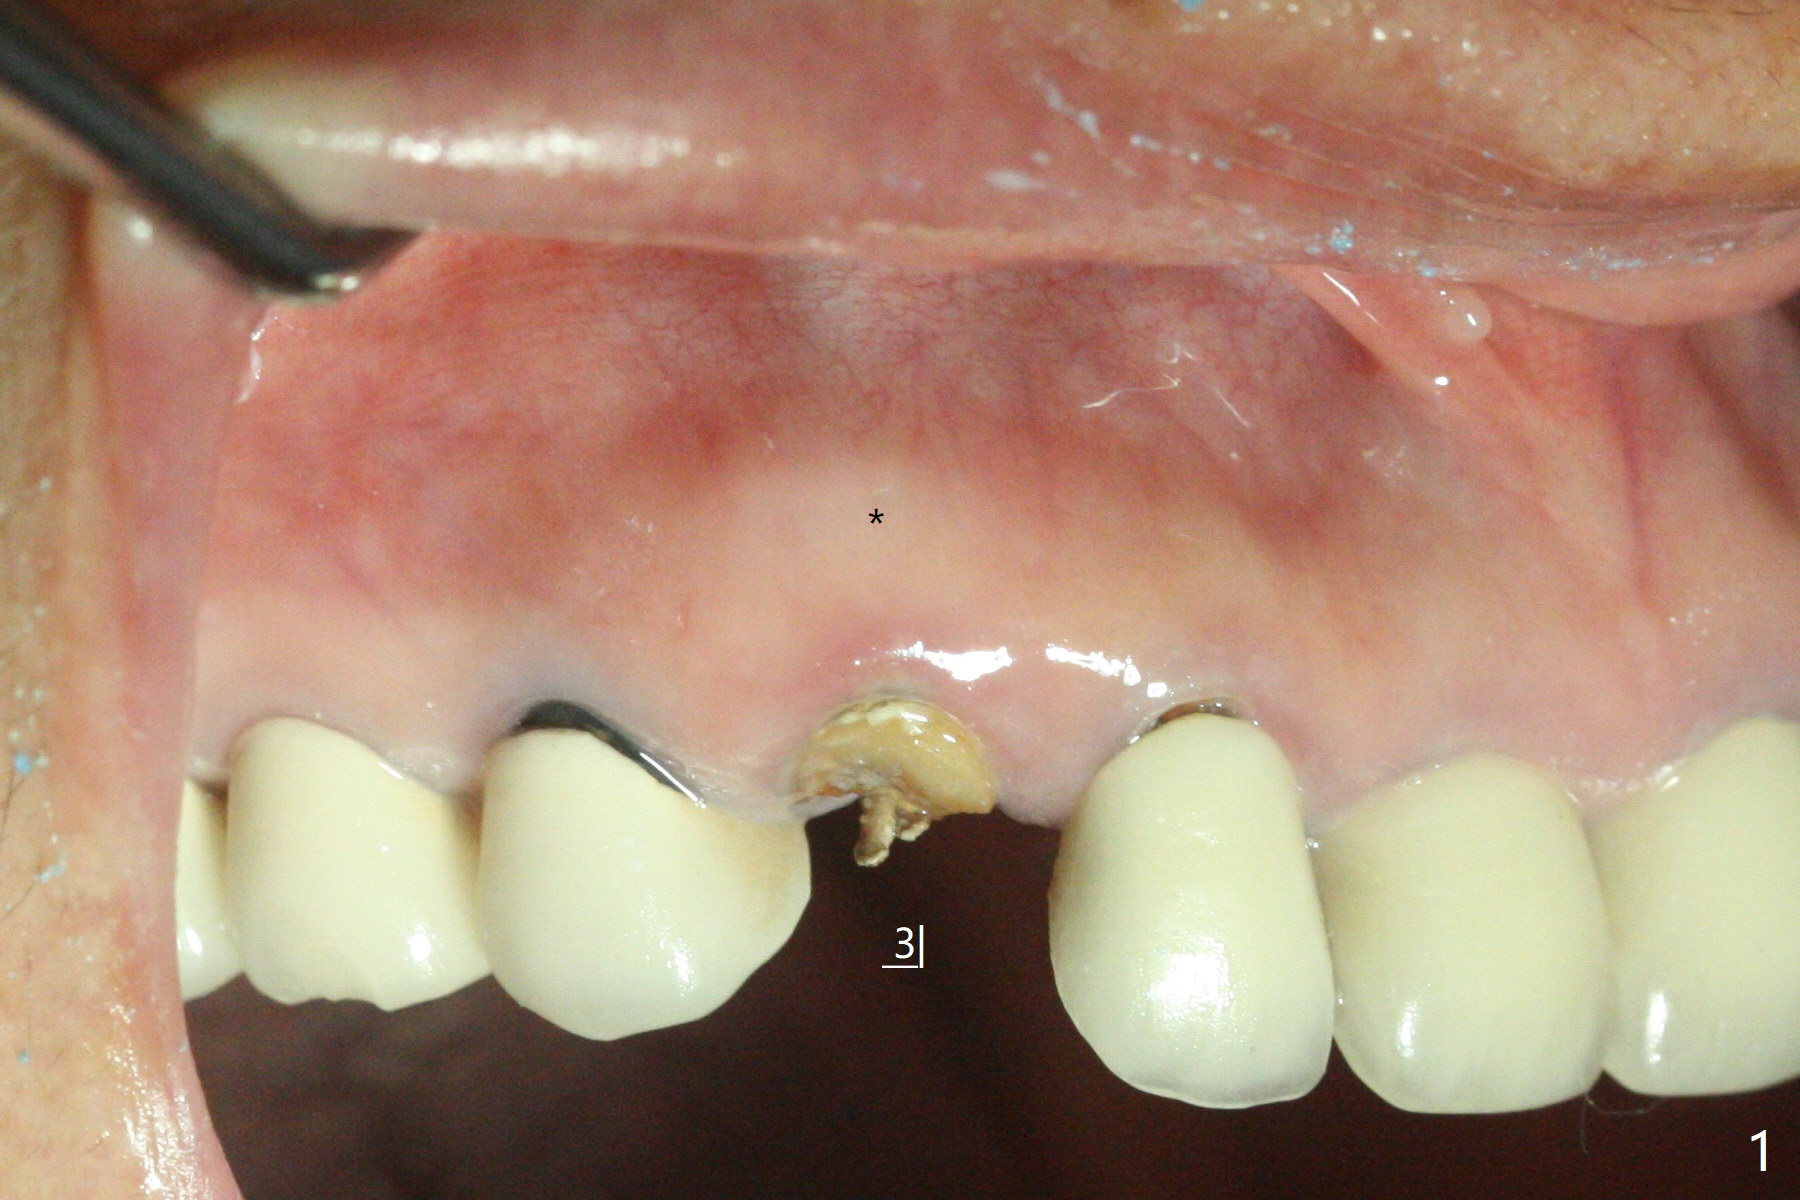

防止拔牙后颊侧骨板萎缩最有效方法是保留部分牙根,例如颊侧(外形象盾牌,简称盾,socket shield (S)),但是制备特别麻烦,尤其是上尖牙。60岁女右上3颊侧骨板隆起(图一至三:*),但是相当狭窄(上下方向),预计强行拔除,势必损失颊侧骨板,造成颊侧塌陷,准备保留盾,如图三红虚线,图六(术后3D长轴断面(十字架:植体))S代表。其实术中试图将整个牙根一起拔除,但是仿佛不行,只好静下心来分根,制备盾,不过困难重重,尤其是除去根尖(防止残余感染),最长外科裂钻似乎达不到根尖,取出后者,颊侧根尖骨板穿孔(图七:箭头)。然后腭侧钻洞(图四),当最后一个钻头保持原位时,在颊侧根尖穿孔处植入粘性骨粉(从牙槽窝口进入,原本粘性骨粉为了修复大面积颊侧缺损用(万一需要强行拔除)),然后才把一段式植体植入(图五),在其余空间填入骨粉,稍微制备基台,制作临时牙冠,最后在牙槽窝开口塞入PRF膜,衬里牙冠,不暂时取出牙冠,衬里相当于临时粘固剂。术后一个月牙根片段和临时牙冠维持良好的牙龈外形(图八,九);术后两个月病人嫌尖牙龈端太尖太长,临时牙冠龈端调整(图十,十一),但愿一个月后龈缘合乎病人期望。